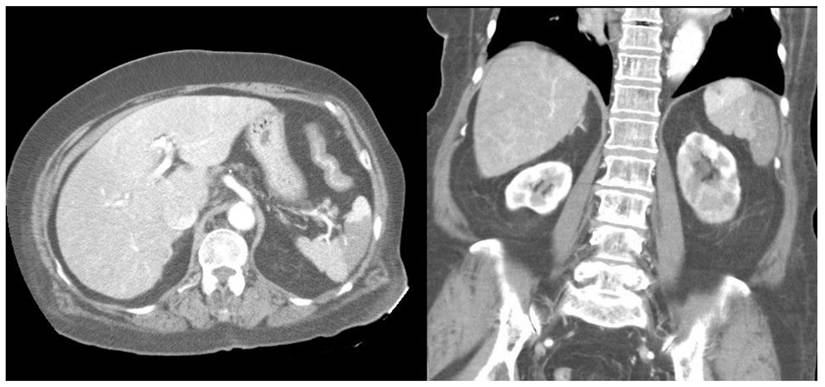

Furthermore, compared with survivors, the non-survivors exhibited significantly higher rates of left-sided pleural effusion, peri-splenic ascites, multiple or total infarction, main portal vein thrombosis, and splenic vein thrombosis on CT imaging. Co-infarctions most commonly involved the kidneys, brain, and intestines. At least one organ co-infarction occurred in 30.6% of cases, while 11.5% experienced two or more, but no significant group differences were observed (Table S4). Figure 2 shows concurrent splenic and left renal infarction, whereas Figure 3 shows splenic infarction with portal vein thrombosis and ascites in a patient with hepatocellular carcinoma.

Figure 2

Concurrent splenic and left renal infarction. Contrast-enhanced abdominal CT images showing wedge-shaped hypodense regions within the spleen on the axial view (left panel) and within both the spleen and the left kidney on the coronal view (right panel).